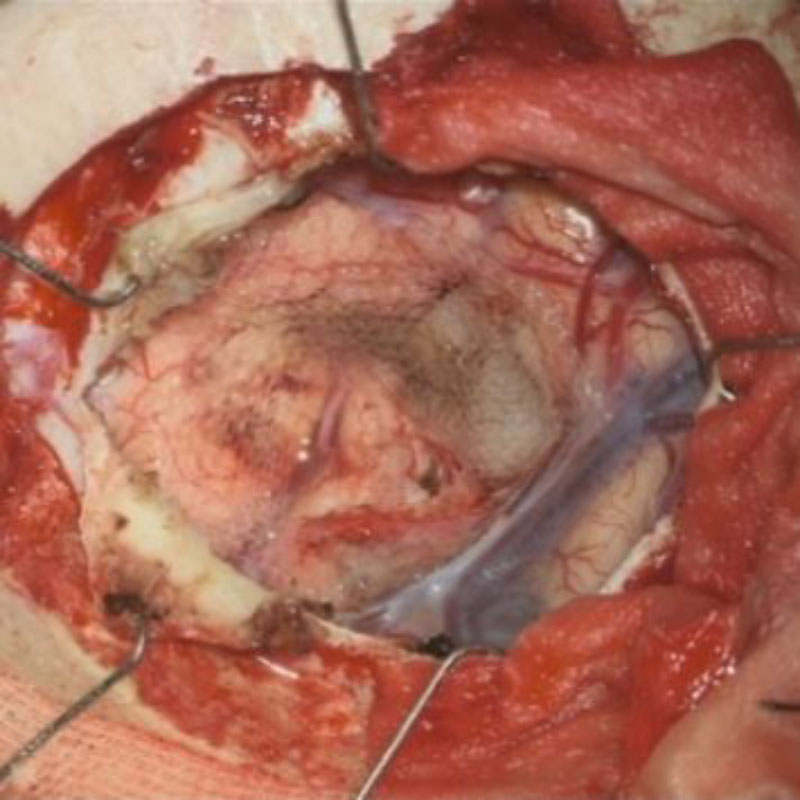

684

'25年10月

50代

右小脳静脈性血管腫

頭蓋内腫瘍摘出術

No.’25_86 手術前1

No.’25_86 手術前2

No.’25_86 摘出 前

No.’25_86  摘出 中

No.’25_86 摘出 後